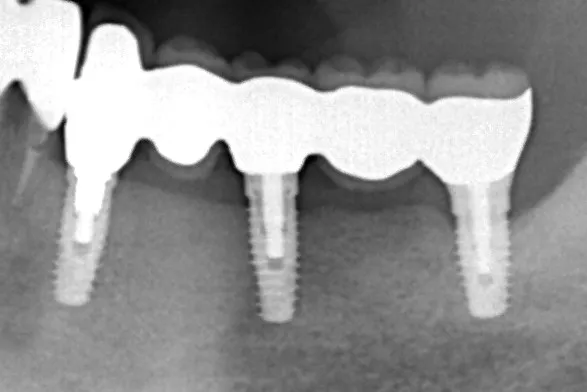

左下5本欠損した部分をインプラント3本埋入して5本ブリッジで治したケースです。なかなかインプラントに踏み切れず、長い間入れ歯を使っておられましたが、噛みごたえがなく好きなものが食べれない上に、度々歯茎が痛んでは調整の繰り返しで快適に過ごすことができず、QOLの向上のためインプラント治療を決断されました。今ではなんでも食べれるとのことで、入れ歯で我慢しないでもっと早くインプラントにすればよかったと言っておられます。